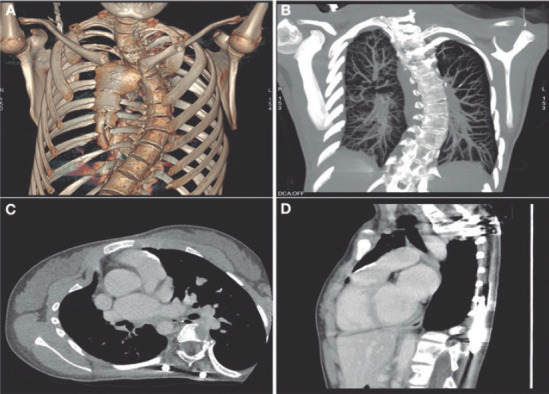

Abstract Image